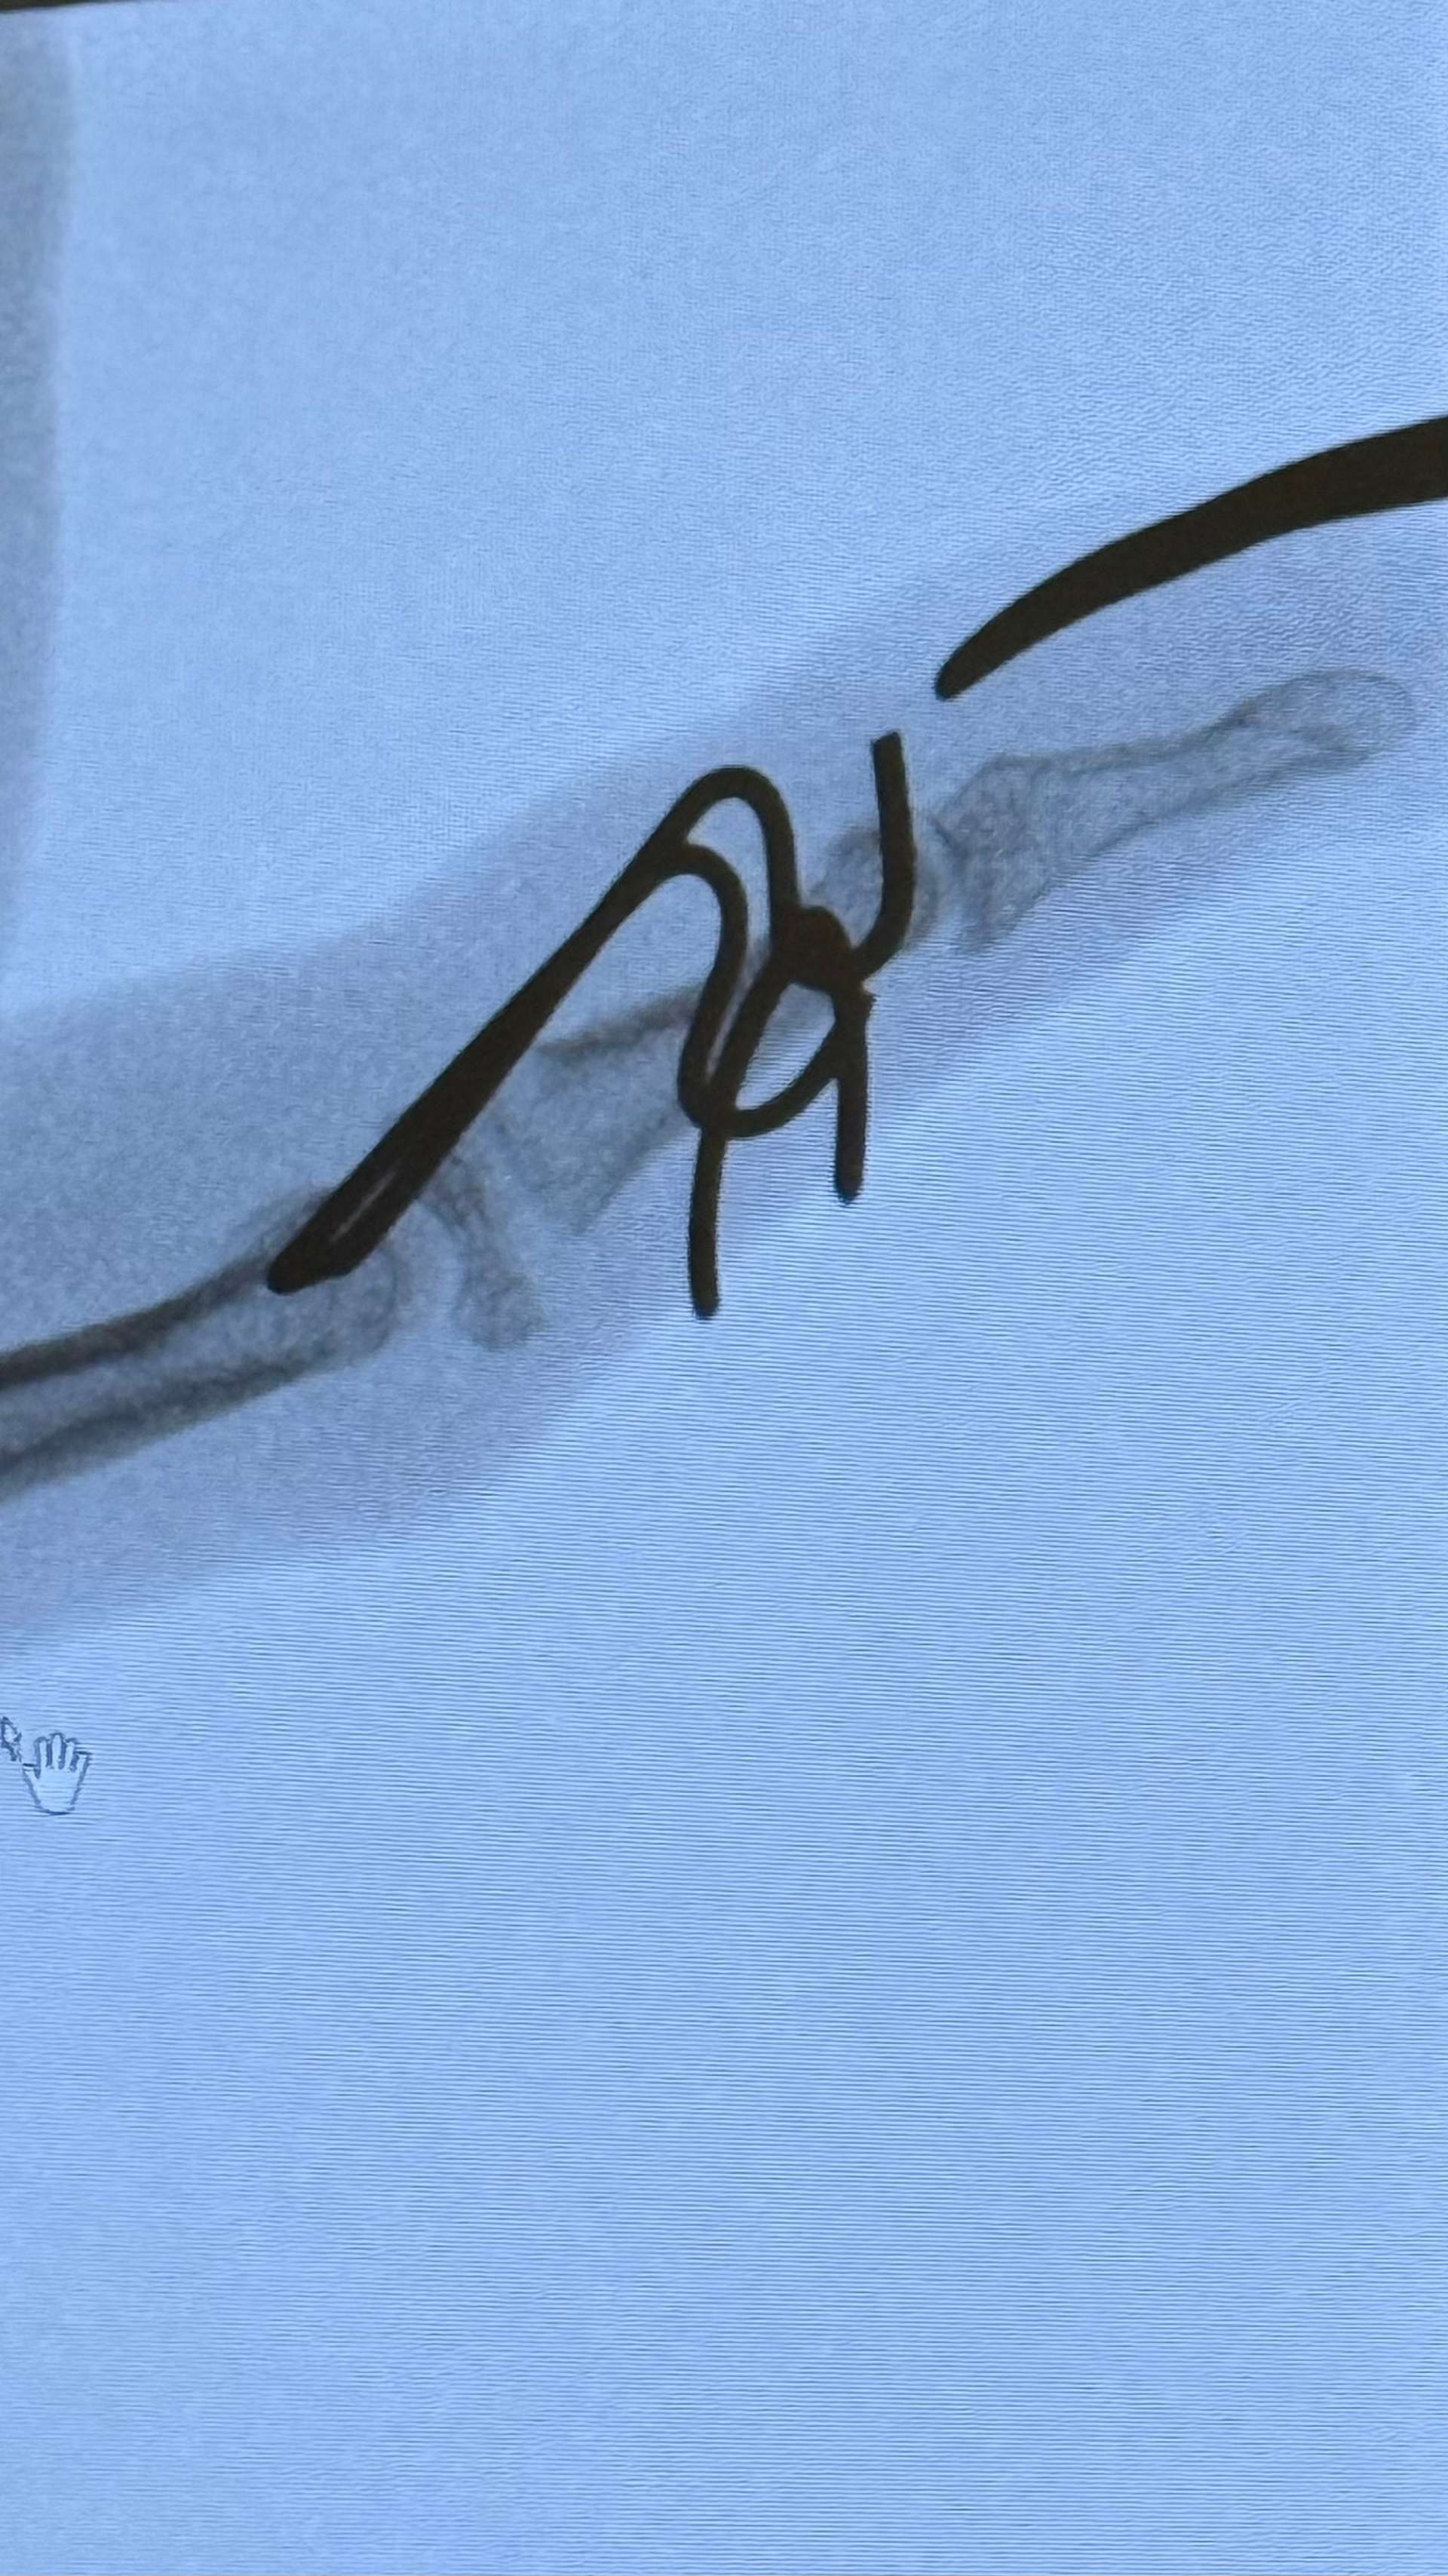

One thing that definitely threw a spanner in our summer plans was an accidental (old man) fall in the dark which left me with a very awkwardly broken little finger. I assumed it was just bruised, but three days later an X-ray confirmed otherwise, complicated enough that I was referred to a hand surgeon, who promptly fitted me with a Giddens frame.

Giddens frame x-ray

Nursing a broken finger in the heat

The timing couldn’t have been worse, the surgery landed on day one of our three-week Rhodes holiday (for our 20th wedding anniversary no less), which naturally upset the family. It meant no swimming, bathing or driving for me, but it did force me to properly slow down and relax. After five weeks the frame was removed, and since then it’s been a weekly physio routine, trying to coax the finger tip back into some flexibility after the bone healed slightly the wrong way.